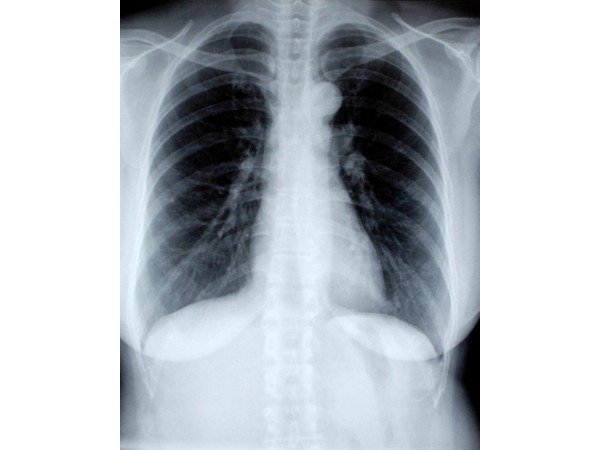

- X-ray: To view the spread of the infection in the lungs and also to rule out other conditions.